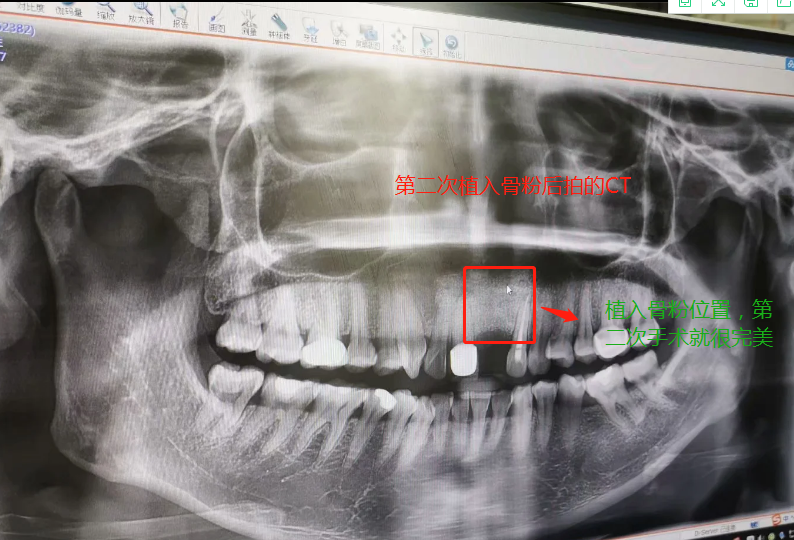

第二次做完植入手術(shù)后拍的CT

2019年7月27日做了種植骨粉手術(shù),在醫(yī)院要等半個(gè)小時(shí)留意一下是否有出血情況,沒有就可以回家休息。做手術(shù)是自己一個(gè)人坐地鐵來回的,勇敢吧。第一天嘴里都是血,第二第三天也是,臉也腫起來,也會(huì)有一點(diǎn)點(diǎn)骨粉掉出來,我那幾天都是喝粥和喝湯,第四天才敢吃飯,第七天傷口就好了,可以帶上臨時(shí)假牙,因?yàn)槲沂巧项€門牙,上顎骨頭密度沒有那么好,正常要等4個(gè)月左右,我的骨粉還是種植的,不是自身的骨頭,所以必須要等半年才能種種植牙。等到2020年1月26日去種植牙根的時(shí)候,那個(gè)主任已經(jīng)調(diào)去別的分店,第一次補(bǔ)完骨粉我就發(fā)覺里面還有個(gè)小洞,問醫(yī)生里面為什么有個(gè)洞的,醫(yī)生說沒事的。我打算去分店種植牙齒的,以為跟我那個(gè)醫(yī)生會(huì)比較了解我情況,后來那個(gè)的助理叫我不要去分店弄了,在這里安排個(gè)專家給我看。經(jīng)過專家的診斷,我還有個(gè)洞沒有補(bǔ)到骨粉,需要再做個(gè)補(bǔ)骨粉手術(shù)后等半年看看情況能不能種牙再說。我聽了真想哭起來,大門牙好不容易空半年可以種牙了,結(jié)果還要我補(bǔ)骨粉,還要等那么長時(shí)間。經(jīng)過跟這家醫(yī)院醫(yī)生溝通和別的門診醫(yī)生回答,決定還是回到這家醫(yī)院做修復(fù),跟助理談了價(jià)格,他說就收取800元,補(bǔ)0.5克骨粉。于是就開始了第二次手術(shù),第一次手術(shù)補(bǔ)了0.5克骨粉(2個(gè)單位,0.25克為一個(gè)單位),第二次補(bǔ)了0.75克骨粉,本來是0.5克骨粉,醫(yī)生做手術(shù)的時(shí)候說還有點(diǎn)間隙,還需要0.25克骨粉,問我要不要加,我說加,就算要另外收費(fèi),我也要加,我的牙齒受的折磨太多了。我要好好弄好這顆牙齒,就收了800元,也沒有額外收0.25克的骨粉錢。我在這家口腔醫(yī)院花了6800元種植骨粉,第二次骨粉植入傷口比較大,醫(yī)生說恢復(fù)期要12天,確實(shí)7天傷口還是沒有恢復(fù)的很好。而且今年1月底爆發(fā)疫情,1月31日領(lǐng)導(dǎo)就讓我們上班,我們公司是做醫(yī)療設(shè)備。傷口都沒有完全康復(fù)就堅(jiān)持上班了。